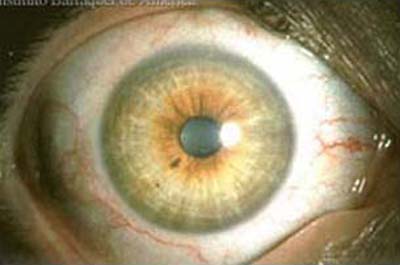

Ojo Sano